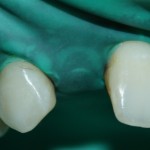

Это может быть просто композитная консоль, изготовленная прямым методом, прямо в клинике и сразу после удаления:

либо лабораторно изготовленный временный протез с опорой на соседние зубы: